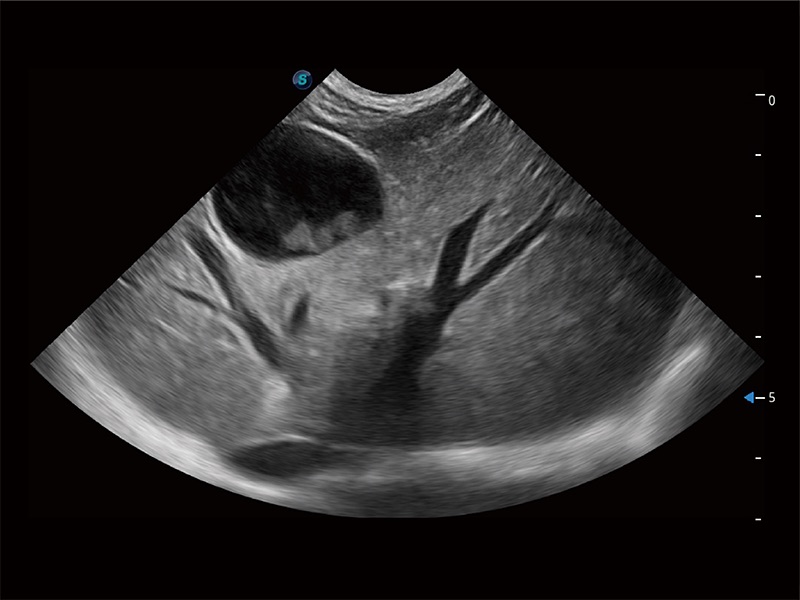

优异的基础图像

ProPet 80 全新的动物超声智能软件和丰富的探头群,为动物医生提供了高清晰度和精细分辨率的图像,无论在宠物、马科、畜牧还是实验室动物等应用中都可以轻松应对,为您的日常工作带来满意的体验。

(犬)肝脏

(犬)胎儿主动脉弓立体血流

(犬)胎儿四腔心